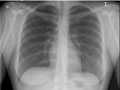

days. Chest X-ray Normal: | The lungs look normal in size

and shape, and the lung tissue looks normal. No growths or other masses can be

seen within the lungs. The

pleural spaces (the spaces surrounding the lungs) also look normal. |

The heart looks normal in

size, shape, and the heart tissue looks normal. The blood vessels leading to

and from the heart also are normal in size, shape, and appearance. | The bones including the spine

and ribs look normal. | The

diaphragm looks normal in shape and

location. | No abnormal collection of

fluid or air is seen, and no foreign objects are seen. | All tubes, catheters, or other